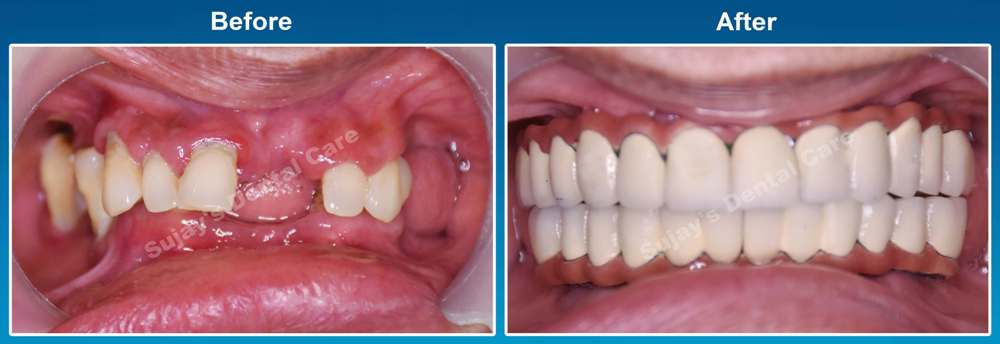

Before & After